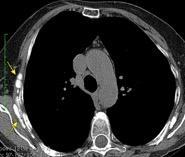

Masa axilar izquierda y derrame pleural derecho. Implantes pleurales, paraespinales . Ganglios en mamaria interna. Linfoma B difuso

Linfoma NH de cél. B. Invasión Transtorácica.

Afectación axilar